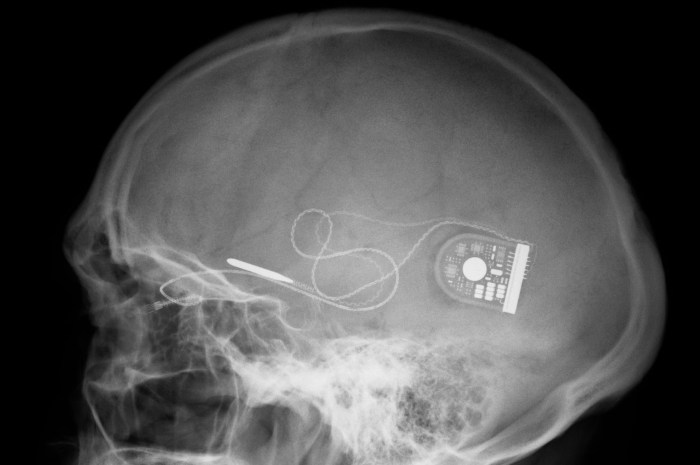

electrx-darpaThe ElectRx program will focus the relatively new area of medical therapies called neuromodulation, which seeks to modulate the nervous system to improve neurological problem. Notable examples of this are cochlear implants which restore hearing by modulating your brain’s auditory nerve system, and deep brain stimulation (DBS) which is apparently capable of curing/regulating conditions  like depression and Parkinson’s by overriding erroneous neural spikes.

So far, these implants have been fairly large, which makes implantation fairly invasive and risky. Most state-of-the-art implants also lack precision, with most placing the stimulating electrodes in roughly the right area, but which are unable to target a specific bundles of nerves. With ElectRx, DARPA wants to miniaturize these neuromodulation implants so that they’re the same size as a nerve fiber.

electrx-darpa-implant-diagramThis way they can be implanted with a minimally invasive procedure (through a needle) and attached to specific nerve fibers, for very precise stimulation. While these implants can’t regulate every condition or replace every medication (yet), they could be very effective at mitigating a large number of conditions. A large number of conditions are caused by the nervous system misfiring, like inflammatory diseases, brain and mental health disorders.